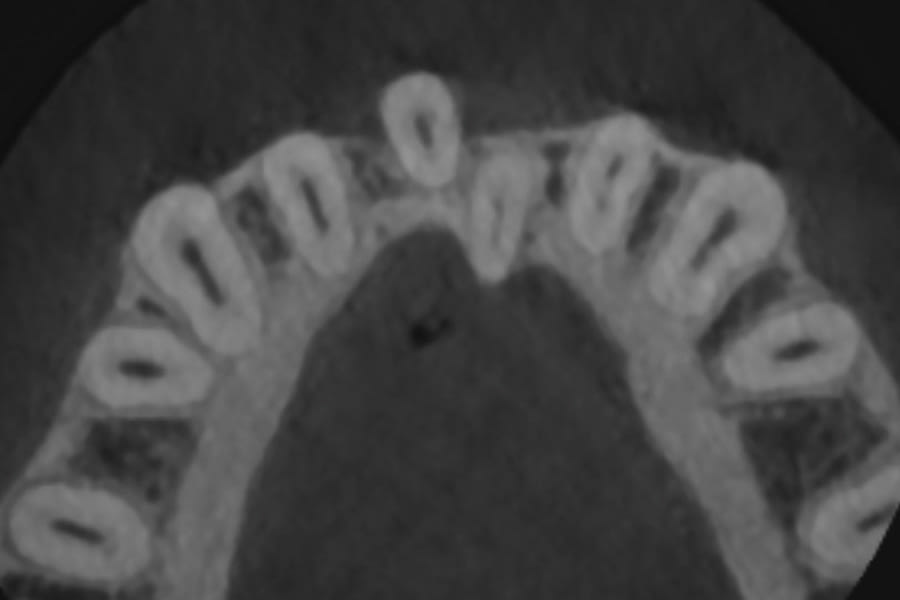

A second alternative is a laboratory-processed nickel-titanium splint (Figure 3) (Memotain®, AOA Lab, aoaaccess.com). The splint is manufactured via laser etching from a sheet of material conforming to a digital impression that is sent to a laboratory. Because the wire is not bent from stock, it is passive in nature and has no uncoiling tendency. It conforms accurately to tooth surfaces and is comfortable due to its streamlined design and intimate conformity. These characteristics also make it suitable as a splint when teeth are imperfectly aligned, as in a periodontally involved crowded dentition (Figure 4). Drawbacks of this design are the time and expense of laboratory fabrication.